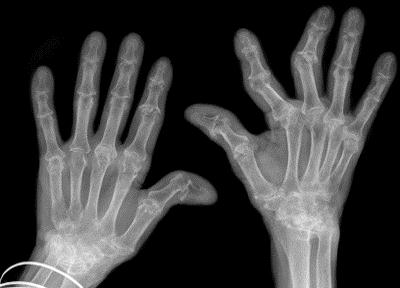

Локализация воспалительного процесса и характер деформаций суставов также имеет важное диагностическое значение. При ревматоидном артрите первые признаки воспаления затрагивают второй и третий пястно-фаланговые суставы и третий проксимальный межфаланговый сустав. Позже патологический процесс распространяется на дистальные межфаланговые суставы, а затем на костно-суставные структуры запястья, а также шиловидный отросток локтевой кости. Поражение суставов обычно носит симметричный характер. На поздних стадиях заболевания наблюдаются характерные деформации кисти: искривления пальцев по типу «бутоньерки» или «лебединой шеи», веретеновидная форма кисти и ульнарные деформации, вызванные частичными вывихами пястно-фаланговых суставов.

В отличие от предыдущего типа заболевания эта патология в первую очередь поражает именно мелкие суставы кистей, а в основе ее патогенеза лежат аутоиммунные процессы, вынуждающие организм вырабатывать патологические вещества, разрушающие собственные суставные ткани. Первые симптомы ревматоидного артрита пальцев рук обычно обнаруживаются на одном из них, а после распространяются на соседние пальцы.

При отсутствии адекватного лечения в патологический процесс вовлекается все больше пальцевых суставов, их функциональность постепенно снижается и в итоге кисть деформируется и фактически полностью утрачивает свое предназначение. Чаще всего заболевание протекает симметрично, то есть поражает обе руки одновременно. Негативные симптомы ревматоидного артрита не ограничиваются только суставами и со временем могут приводить к тяжелым расстройствам в работе многих внутренних органов (почки, сосуды, легкие и пр.).

Формируется на фоне такого серьезного заболевание как псориаз и по своей сути является одним из его негативных проявлений. При поражении кистей в этом случае, как правило, страдают их дистальные суставы или все суставы одного пальца одновременно. Типичным симптомом этого вида патологии считается багрово-синюшный оттенок кожных покровов над проблемными зонами и выраженная опухлость. При этом поврежденные пальцы по виду напоминают вареные сосиски, а сами суставы становятся похожи на редиску.

- Поврежденные артритом пальцевые суставы фактически во всех случаях опухают и/или отекают, что иногда делает пальцы на руках отдаленно похожими на чурчхелу. Кроме того, кожные покровы вокруг костяшек поврежденных пальцев краснеют, натягиваются и становятся горячими на ощупь.